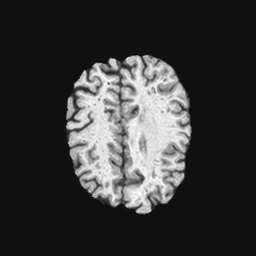

Exp. 2: Fetal brain data is used to test the robustness of our approach under real conditions. Fetuses younger than 30 weeks very often move a lot during examination. Fast MRI sequences allow artifact free acquisition of individual slices but motion between slices corrupts consistent 3D information. Fig. 3 shows that our method is able to accurately predict also under these conditions. For this experiment we use from three orthogonally overlapping stacks of ssFSE slices covering the fetal brain with approximately 20-30 slices each. We are ignoring the stack transformations relative to the scanner and treat each individually. For , 28 clinically approved motion compensated brain reconstructions are resampled into a volume with spacing. A density of 500 unique sampling normals has been chosen via the Fibonacci sphere sampling method with 25 sampling planes evenly spaced between -25 to +25 on the Z-axis. This gives a plane spacing of 2mm, sampling only the middle portion of the fetal brain. Training took approximately 10hrs for 30 epochs. Prediction, i.e., the forward pass through the network, takes approx. 12 ms/slice.

0..5 Randomly selected illustrative inference results

Here we show for Exp. 1, Exp. 2, and Exp. 3 randomly selected examples of images that have been presented to the network (ground truth) compared to an image sampled at the predicted location.

In these experiments, we present a ground truth (GT) image to the network to estimate the respective transformation parameters needed to reorient the slice in its correct world co-ordinates. Using the transformation parameters, we generated a slice from the 3D atlas in the location where the network has predicted that slice should be (denoted as SVRNet).

The slices are compared side-by-side to give a visual representation of “where the slice really is” and “where the network thinks the slice is”.

0..5.2 Exp. 2:

Slices, from a motion corrupted MRI stack, are segmented and cropped. Since there is no ground truth for the queried images, an arbitrary fetal atlas is used for visualization in Fig. 11 and 12.